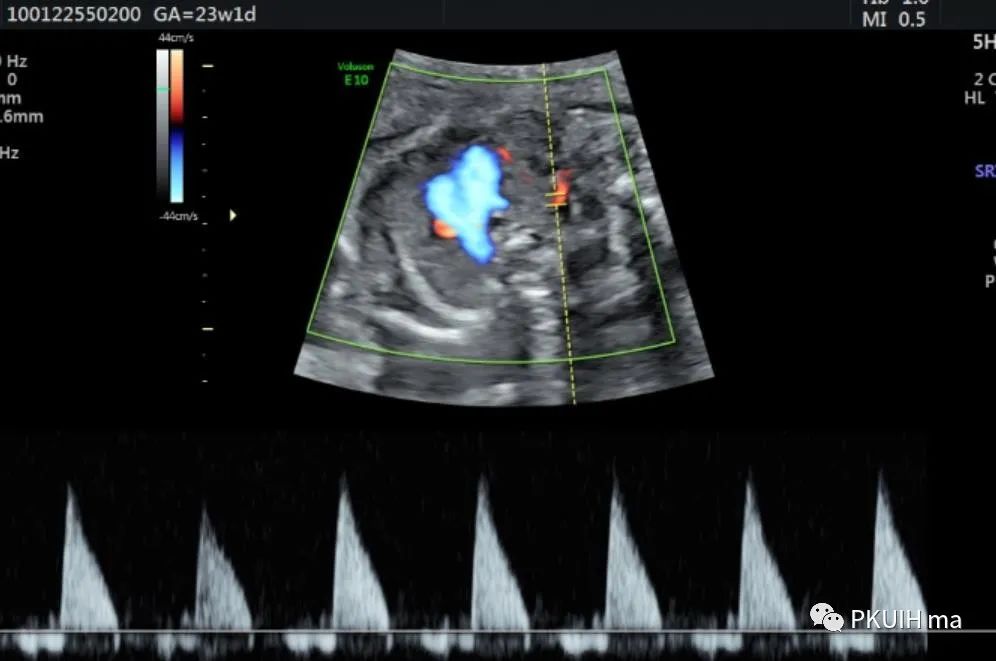

锁骨下动脉观察一般在主动脉弓水平横切面观察,显示左右锁骨下动脉像弓箭样向左右肩部走形。对于迷走的锁骨下动脉观察需要在三血管气管切面和主动脉冠状切面观察。右锁骨下动脉迷走在三血管气管切面可见一血管于主动脉弓降部发出自脊柱前方气管后方向右肩走行,在主动脉冠状切面显示主动脉弓降部见一血管迂曲向右肩部走行,频谱显示为动脉频谱。右锁骨下动脉迷走在三血管气管切面要和左无名静脉鉴别,左无名静脉汇入上腔静脉,频谱为静脉频谱,同时右锁骨下动脉也要和走形于气管后方汇入上腔静脉的奇静脉相鉴别,血流频谱有助于两者鉴别。

脊柱前方一红色血管为迷走的右锁骨下动脉,频谱为动脉频谱